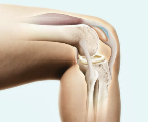

무릎이 뻐근하거나 계단을 오를 때마다 ‘찡’한 통증이 느껴진다면,

아마도 한 번쯤은 글루코사민이나 콘드로이친에 대해 들어보셨을 거예요.

두 성분 모두 관절 건강을 위한 대표 보충제로 많이 알려져 있지만,

실제로는 기능, 작용 방식, 복용 시기, 흡수력까지 서로 다른 부분이 많습니다.